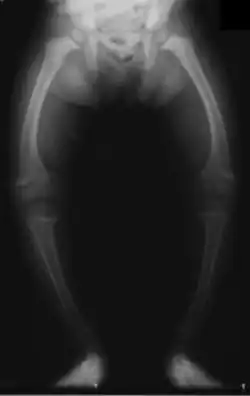

Fetuses and children who do not get enough vitamin D can result in "growth retardation and skeletal deformities."[23]